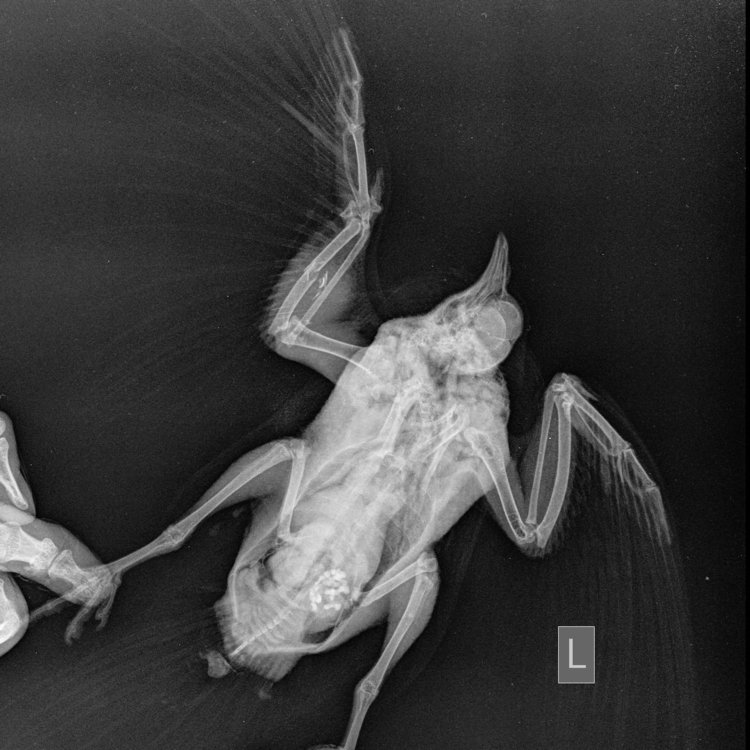

Zosia Опубликовано 29 июля, 2021 #15 Опубликовано 29 июля, 2021 Вам надо сделать еще раз снимок, с аккуратно и полностью раскрытым поврежденным крылом. Фиксировать к основанию (над кассетой) бумажным скотчем, придерживать крыло у плеча. Потому что на вашем первом снимке- полный многооскольчатый перелом локтевой кости с малым смещением, а вот лучевая кость выглядить выбитой (оторванной), что озанчает внутрисуставный перелом...Но т.к. крыло снято не в раскрытом состоянии- степень повреждения оценить трудно. Что там с легкими- а что-то есть- так же плохо видно. С успехом это м.б. микоплазмоз, или клебсиелльная пневмония, или тупо аллергическая реакция на что-то. Глубокий мазок из глотки и помет- и красить по Циль-Нильсену. Смотреть КУМ и криптоспоридии. Ну и банальный общий анализ помета (копрограмма) Пока основная терапия- снятие боли (НПВС), травматин, миорелаксант можно (толперизон). Фиксация - магкая, в сетчатый трубчатый бинт, со свободным здоровым крылом. Вот аткого типа: https://public.fotki.com/Shemlik/bae5/b70c.html https://public.fotki.com/Shemlik/bae5/2.html#media https://public.fotki.com/Shemlik/bae5/3.html#media

Cara Mia Опубликовано 4 августа, 2021 Автор #17 Опубликовано 4 августа, 2021 Добрый день! Снимки нового рентгена голубя были сделаны в клинике "Главное Хвост". Лечащий врач этой клинике после осмотра и на основании этих снимков сделала такую выписку (фото) с диагнозом (диф.) Аэросаккулит, (диф.) Аэроцистит. По перелому сказала, что оба крыла работают, оно начинает срастаться, но необходимо извлечь остатки раздробленной кости, для чего нужна операция, а вывихи вправлять в Беларуси не могут. Посоветовала записаться на прием к главному врачу-орнитологу клиники А. Полозу, который до 14.08. находится в отпуске. Назначены следующие препараты: 1. Амоксициллин 250 мг - внутрь по 1/16 содержимого капсулы 1 раз в день, на протяжении 10 дней. 2. Мелоксидил сусп. - внутрь по 0,1 мл 1 раз в день, на протяжении 10 дней. 3. Нистатин 500000 ед. - внутрь по 1\6 таблетке 2 раза в день, на протяжении 14 дней. 4. Карсил - внутрь по 1/10 таблетки 1 раз в день на протяжении 14 дней. Не входит ли это в противоречие с уже существующим назначением другого врача?: 1. Ципрофлоксацин, 250 мг, внутрь по 1/10 таблетки 2 раза в день 3 недели (ПРОДОЛЖЕН С 14 ДО 21 ДНЯ ПОСЛЕ ПЕРВЫХ СНИМКОВ РЕНТГЕНА) Курс начат 22.07 Курс будет закончен 12.08 2. Мелоксикам 7.5 мг, внутрь по 1/10 таблетки 1-2 раз в день, 7 дней, далее по состоянию Курс начат 20.07 Курс закончен 27.07 3. Метронидазол 250 мг внутрь по 1/8 таблетки 1 раз в день 5-7 дней Курс начат 20.07 Курс закончен 26.07 4. Нистатин 500000 ед. внутрь по 1/4 таблетки 2 раза в день в течение месяца (ДОБАВЛЕН ПОСЛЕ ПЕРВЫХ СНИМКОВ РЕНТГЕНА) Курс начат 22.07 Курс будет закончен 22.08 5. Празицид, суспензия для котят внутрь по 0.3 мл 2 раза с интервалом 14 дней Курс начат 23.07 Курс будет закончен 07.08 6. Стронгхолд 1/2 пипетки 2 раза с интервалом 21 день Курс начат 18.07 Курс будет закончен 07.08 СОСТОЯНИЕ: Голубь стал беспокойным, постоянно пытается выбраться из контейнера, часто машет крыльями. Ест хорошо, по назначению врача (каши, семена подсолнечника, льна), морковь и салат добавляю,но он не ест почти). Несколько дней назад цвет стула изменился на зеленый (фото), врач связала это с большим количеством медпрепаратов. Во время кормления лекарствами через пипетку сейчас вертит головой, оказывает сопротивление (раньше такого не было). Также при приближении руки убегает, вырывается и немного "кряхтит" (так, как это делают утки). Звук могу скинуть, если нужно. На приложенных гифках он сегодня после приема у врача, в состоянии стресса. Также Ахова птушак Бацькаўшчыны (@apb_birdlife_belarus посоветовала мне связаться с Зоей Кенько. Спасибо ей большое, что она сразу же ответила, и помогла с расшифровкой назначений, а также с контактами хороших хирургов и терапевта для проведения операции. АНАЛИЗЫ: На анализы есть возможность записаться в субботу, этого врача советуют консультант Зоя Кенько и Валерия Сороко (ВетТаргет). Стоит ли ждать продолжать курс, менять курс лечения, не дожидаясь анализов (мазок из зоба, копрограмма) до субботы хорошего врача (Вересовая Екатерина)? К сожалению, в других клиниках или не делают эти анализы, или (по отзывам волонтеров и хозяевов) делают их не совсем качественно. Прошу Вас помочь с диагностикой голубка и спасибо большое за помощь! @Zosia @OFA @маленький принц